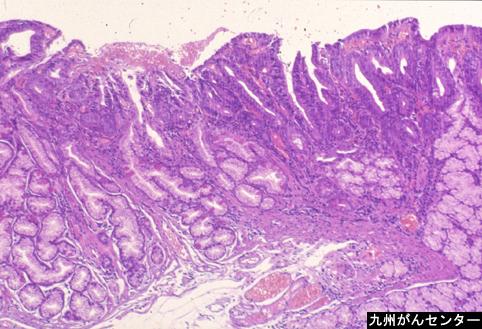

疾病(病理主体)的分类良性上皮性肿瘤/腺瘤

部位(按器官分)十二指肠/水平脚

检查方法病理切片(微观)

肿瘤的肉眼分类0型(表在型)/IIa型(IIa+IIc)

肿瘤最大直径10~14